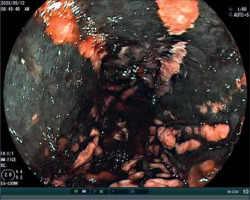

Endoscopy was performed in 176 patients with corrosive substance intake. The most severe endoscopy findings (high-grade injury) were significantly associated with acid and base ingestion in all 3 endoscopy sites (Table II; Figures 1–3).

Figure 2

Endoscopic finding of stomach in female after ingestion of hydrochloric acid ingestion (grade III)